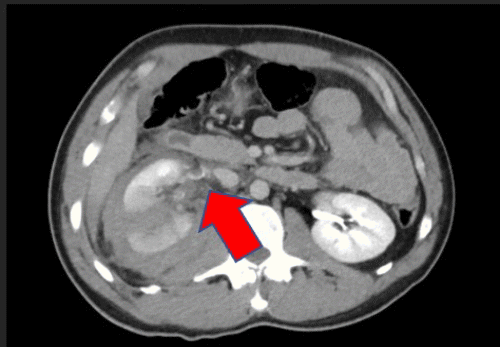

A 31-year-old male trauma transfer from another hospital sustained blunt abdominal trauma following a snowboarding accident. The referring hospital's CT scan revealed a liver laceration (grade IV), extensive right kidney injury (grade IV) with a perinephric hematoma, possible damage to the right renal collecting system with extravasation of urine, and a fractured 10th right rib (Figure 1).

Figure 1. Preoperative Imaging Findings. Published with Permission

A) Grade IV liver laceration.